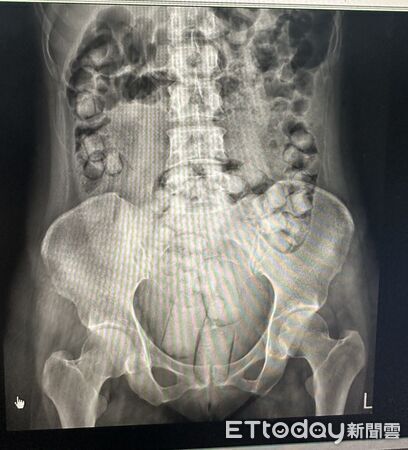

▲2名泰籍女子體內塞了664公克海洛英。

海巡人員表示,小顆的加橄欖油吞食,大顆的加潤滑劑塞肛門,A女體內有54顆、390.93公克;R女有61顆、273.07公克。